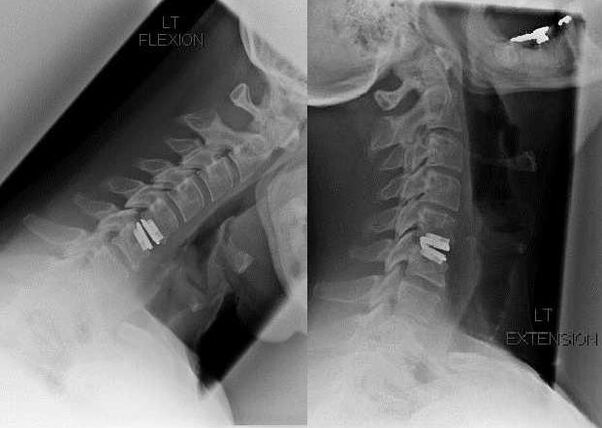

Intervenție chirurgicală

Indicațiile pentru intervenția chirurgicală includ ineficacitatea tratamentului conservator, precum și complicațiile osteocondrozei cervicale, de exemplu, mielopatia discogenică, sindromul arterei vertebrale și sindromul radicular. Pentru a decomprima măduva spinării, vasele de sânge și rădăcinile spinării, se efectuează următoarele operații:

În timpul intervenției chirurgicale, fragmentele osoase și ligamentele pot fi excizate, iar discurile intervertebrale pot fi îndepărtate complet sau parțial. Pentru proeminențe herniare mici, se efectuează adesea vaporizarea cu laser a nucleului discului.

După excizia structurilor vertebrale, stabilizarea segmentelor de mișcare a coloanei vertebrale este adesea necesară prin fuziunea coloanei vertebrale sau instalarea de autogrefe osoase și dermice.